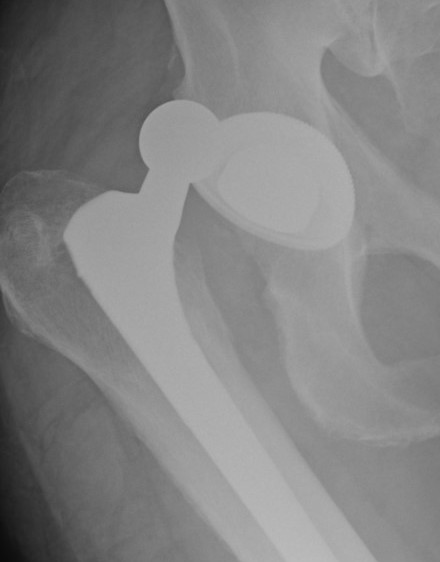

Stryker dual mobility

Concept

Femoral head moves within a poly component, which moves within the fixed acetabulum

- primary motion occurs at the inner bearing

- outer bearing moves in cases of extreme range of motion